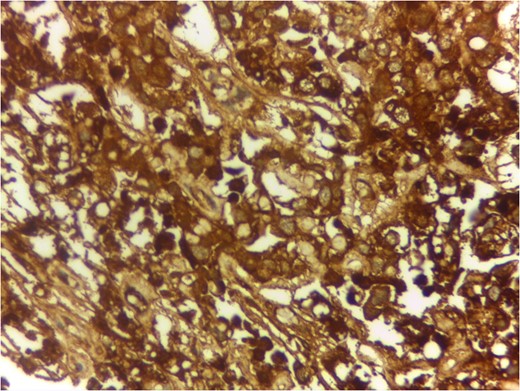

Serum markers on day of surgery were Alpha Feto Protein (AFP) 131 146 ng/ml (normal range 0–20 ng/ml), Beta subunit of Human Chorionic Gonadotropin (beta hCG) 0.5 mIU/ml (normal range < 2 mIU/ml), Lactate Dehydrogenase (LDH) 1231 U/L (normal range 0–850 U/L)

Serum markers, histopathological examination and IHC all three confirmed diagnosis of yolk sac tumour.